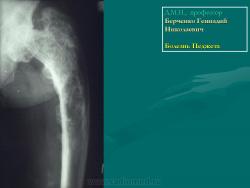

Доктор медицинских наук, профессор   Берченко Геннадий Николаевич

Болезнь Педжета проявляется у больных в возрасте старше 40 лет. Заболеваемость варьирует в пределах 0,1–3% населения. У лиц моложе 40 лет частота заболеваемости не превышает 0,5%, у лиц старше 90 лет частота заболеваемости около 10%. Деформирующий остоз чаще встречается у мужчин. Поражение только одной кости (монооссальная форма), преимущественно большеберцовой, бедренной, или таза встречается редко, в 85% в процесс вовлекается множество костей (длинные кости, кости таза, черепа и позвоночника) ― полиоссальная форма. В основном поражаются кости, несущие наибольшую механическую нагрузку (поясничные и крестцовые позвонки, бедренная и большеберцовые кости и др.); характерны поражения костей крыши черепа; из лицевых костей чаще поражаются челюсти.

Деформирующая остеодистрофия (болезнь Педжета) чаще проявляется у мужчин в возрасте 40-60 лет, характеризуется постепенно прогрессирующим утолщением коркового слоя костей с развитием гиперостозов, деформацией, искривлением костей, беспорядочностью их структуры, образованием в них кист; поражаются кости мозгового черепа, позвоночника и длинных трубча­тых костей. Размеры мозгового черепа увеличиваются, наружная пластинка костей свода черепа местами утолщена, гиперостозы чередуются с участка­ми беспорядочного разрежения кости. В связи с деформацией костных от­верстий и каналов основания черепа и межпозвонковых отверстий наруша­ется функция черепных и спинномозговых нервов, возможны расстройства кровообращения. Деформация глазниц обусловливает экзофтальм. Нередко отмечаются признаки внутричерепной гипертензии. Позвонки сплющены; в трубчатых костях сужены костномозговые каналы, возможны патологические переломы костей, при этом линия перелома четкая, ровная, как при переломе очищенного банана («банановый перелом»); усилены физиологические изгибы позвоночника. Процесс может быть относительно ограниченным или распро­страненным. Содержание кальция и фосфора в крови нормально или слегка увеличено, активность щелочной фосфатазы повышена. Предполагается доми­нантный тип наследования с различной экспрессивностью. Описал болезнь в 1877 г. английский хирург J. Paget (1814-1899).

В монооссальных случаях, частота которых, согласно публикациям, начинается от 10-20% доходя до почти 50%, дифференциальный диагноз может быть гораздо сложнее. В огромном большинстве случаев БП, наличие неоднородных участков костного склероза или остеолиза с искажением трабекулярной архитектуры в сочетании с кортикальным утолщением и фокальным утолщением кости практически патогномоничен для данного заболевания. Бедренная кость является второй наиболее распространенной монооссальной локализацией после таза. В случаях, когда имеется ее дистальное поражение, рентгенологические признаки, характерные для БП, выявляются с меньшей частотой или менее выражены, так что дифференциация с другими процессами, в частности, опухолевыми, может быть затруднена.